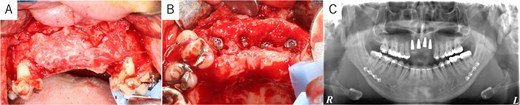

Simulation of dental implant placement in the maxillary anterior region using coDiagnostiX® (Straumann, Basel, Switzerland) revealed insufficient bone volume in both height and width (Fig. 3A). A 3D simulation was performed for bone augmentation in the maxillary anterior region alongside posterior mandibular movement. Mandibular retraction measured 6.2 mm on the right side and 7.0 mm on the left side. DICOM files from dental cone-beam computed tomography were converted to Standard Tesselation Language (STL) data using Volume Extractor® (Volume Extractor 3.0; i-Plants Systems Corporation, Iwate, Japan) (Fig. 3B). Osteotomy lines and the required bone augmentation were established using Geomagic Freeform® (3D Systems, Rock Hill, SC, USA) (Fig. 3C). A 3D model was printed (Straumann® CARES® P20+; Straumann, Basel, Switzerland) from the STL data, and a titanium mesh (Universal Mesh; Stryker Japan, Tokyo, Japan) was shaped to maintain space for PCBM grafting (Fig. 3D). The planned augmentation volume for implant placement was 5.6 mL, with a target bone harvest volume of 9 g, sourced from the right anterior iliac crest. In October 2023, SSRO and bone augmentation were performed simultaneously as planned (Fig. 4A). After harvesting PCBM from the right anterior iliac crest, SSRO was completed. The harvested PCBM was grafted into the bone defect and secured with the pre-bent titanium mesh (Fig. 4B). The wound was sutured, concluding the first operation.

Intraoperative and postoperative images. (A) SSRO surgery was performed with conformity to the orthodontist-prepared final splint. (B) PCBM was grafted into the bone defect and covered with titanium mesh. (C) Postoperative panoramic radiograph showed no abnormalities.

The postoperative panoramic radiograph showed no abnormalities (Fig. 4C). Cone-beam computed tomography images taken 2 months after surgery confirmed the stability of the grafted bone (Fig. 5A). A new simulation for dental implant placement was performed (Fig. 5B–D). At 4 months postoperatively, the titanium mesh was removed, and dental implants were placed. Bone tissue in the defect was confirmed. Implants with a diameter of 4.1 mm and a length of 10 mm (Straumann BLT/RC; Straumann, Basel, Switzerland) were successfully inserted (Fig. 6A–C). Postoperative photographs (Fig. 7) showed improvement in the skeletal mandibular protrusion and a favorable intermaxillary relationship between the upper and lower jaws.